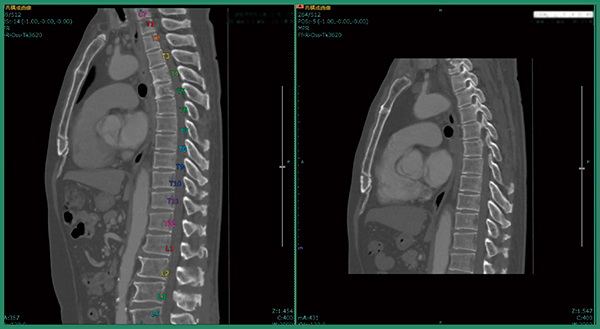

上記検討で判明した問題点を改善するため,AI技術をソフトウエア設計に用いた2つの機能を実装した。1つは骨ラベリング機能で,これにより椎骨番号が自動で認識・表示される。病的骨折で変形,あるいは上下が融合しているような椎骨についても,分離・ラベリングが可能となった。もう1つは位置合わせ機能で,これにより従来版と比べて差分計算が5〜10倍に高速化した。また,汎用性も向上し,肋骨や骨盤なども位置合わせができるようになり,脊椎以外への骨転移の診断にも応用可能である。

症例1は,肺がん術後症例で肺の形が変形しており,撮影範囲も過去画像は胸部のみ,今回画像は胸腹部と大きく異なっていた。改良版ソフトウエアで差分を取ると,溶骨性の骨転移が青く表示され,椎骨が変形している様子もわかる(図2)。また,自動でラベリングされるため,椎骨番号の判断が容易となり,T4,T5であると判断できる(図3)。さらに,T1にも溶骨性の小さな骨転移があることが明瞭にわかる(図4)。

図2 症例1:改良版ソフトウエアによる骨転移候補の検出

図3 症例1:椎骨番号の自動ラベリング

図4 症例1:T1の微小な骨転移候補の検出